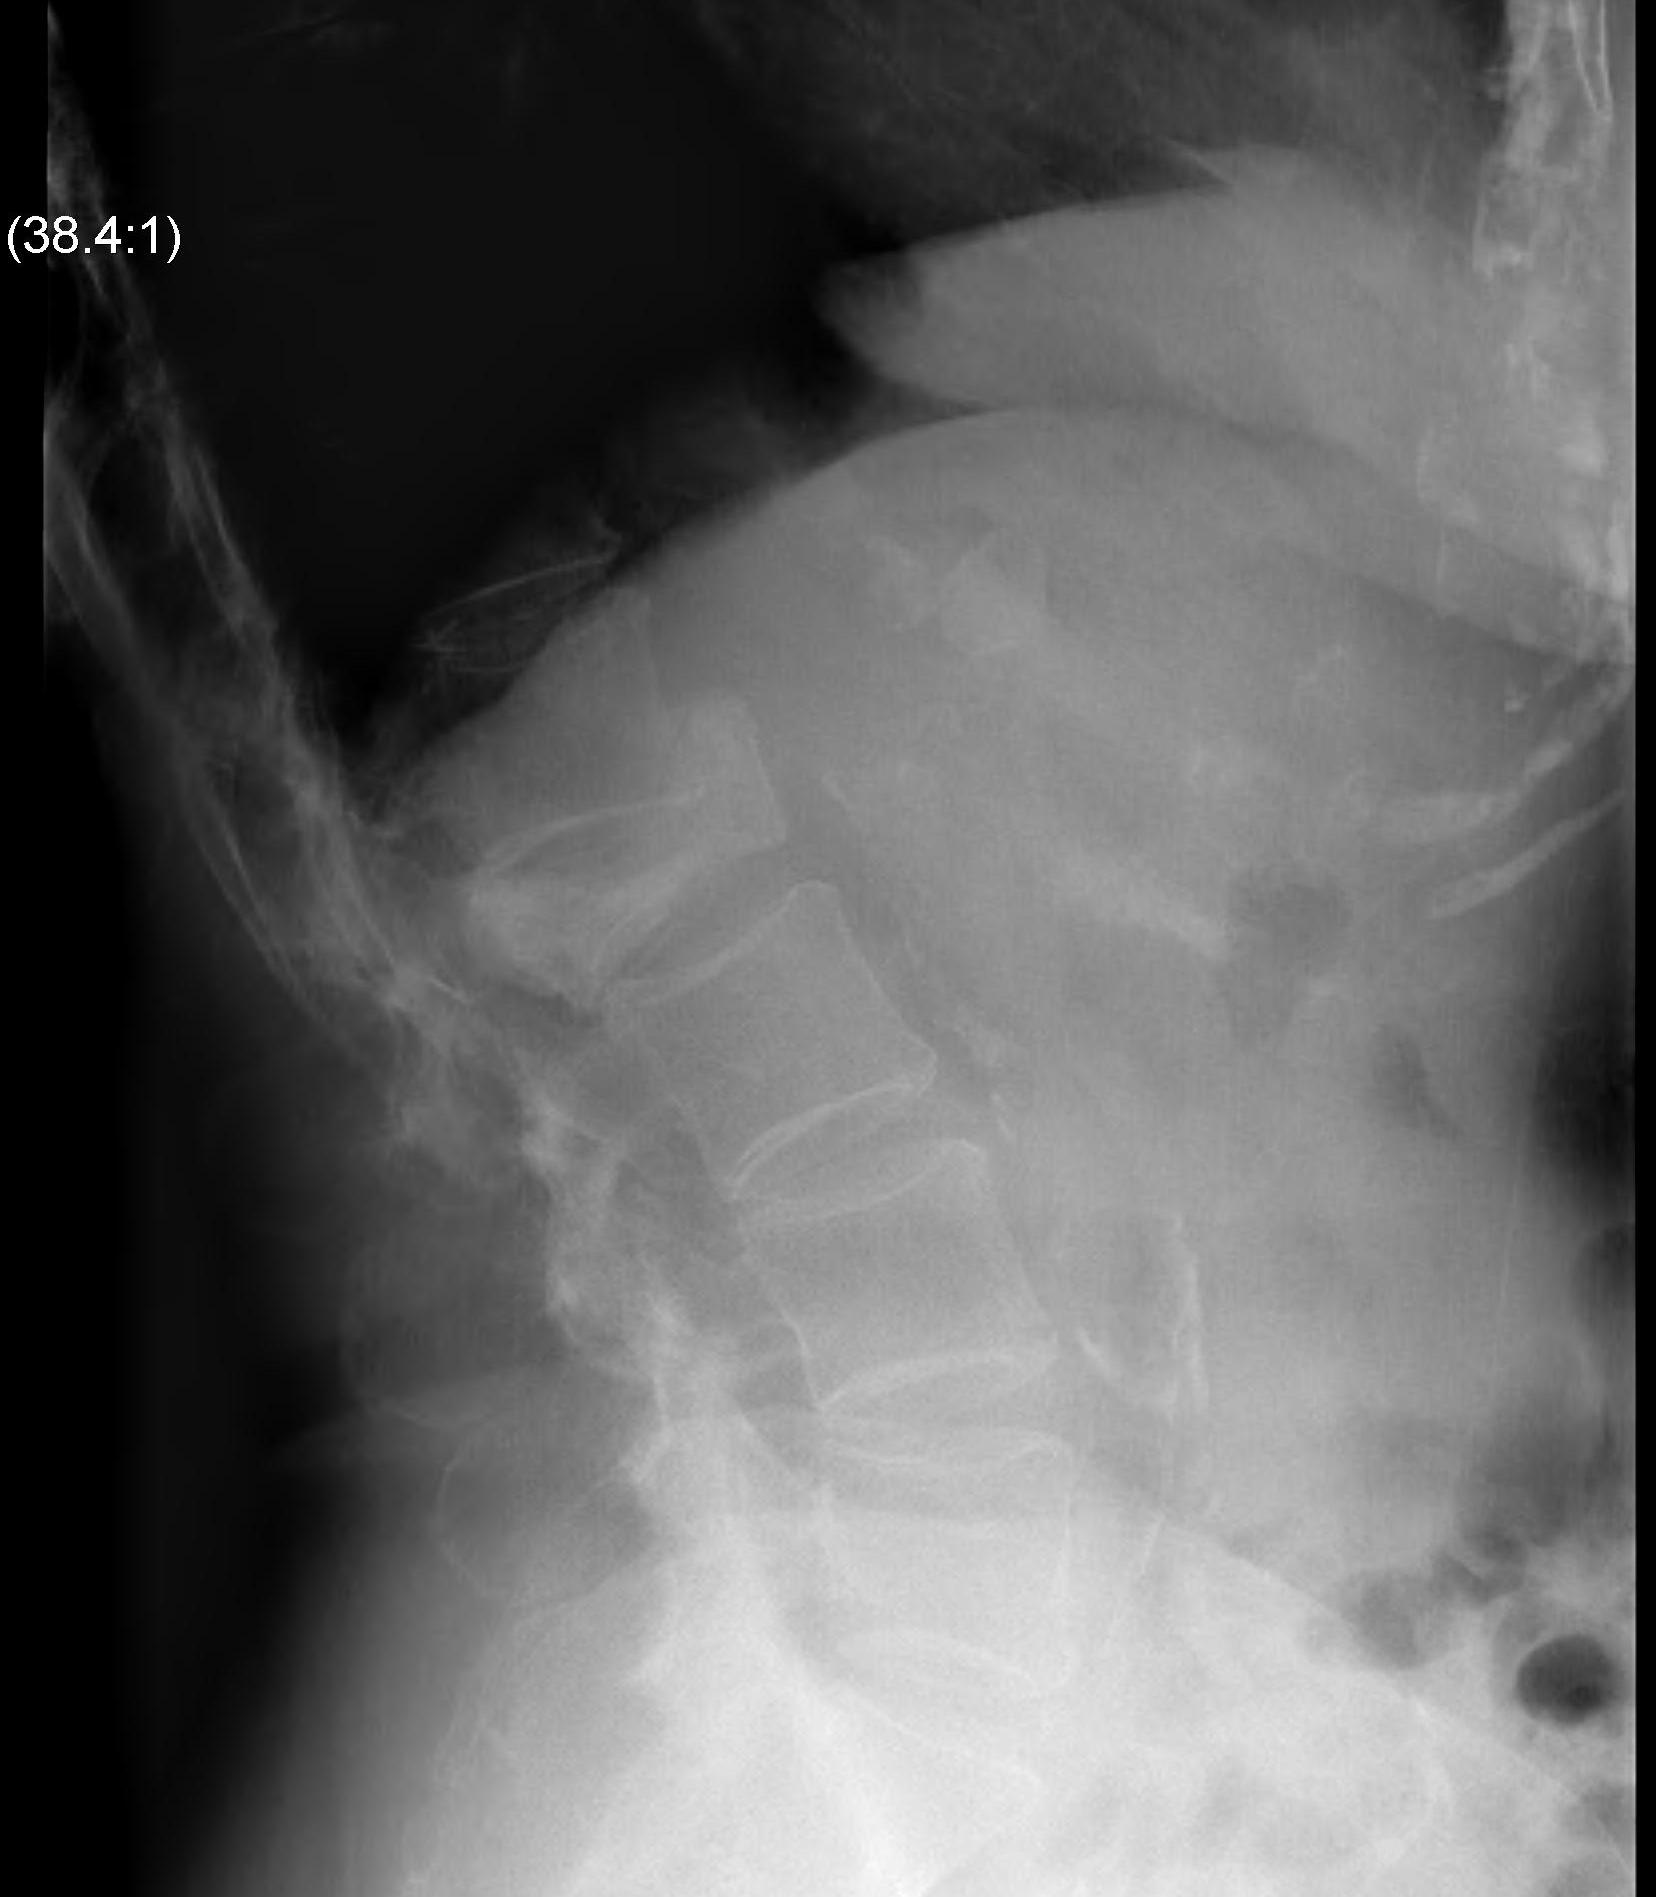

X-ray

75% have abnormality

Winking Owl Sign / Pedicle loss on AP

Lytic / Sclerotic lesion

- need 30% bone loss to see lytic area

Vertebral body collapse

CT Scan

Define

- bony abnormality

- deformity

- potential instability

Lumbar